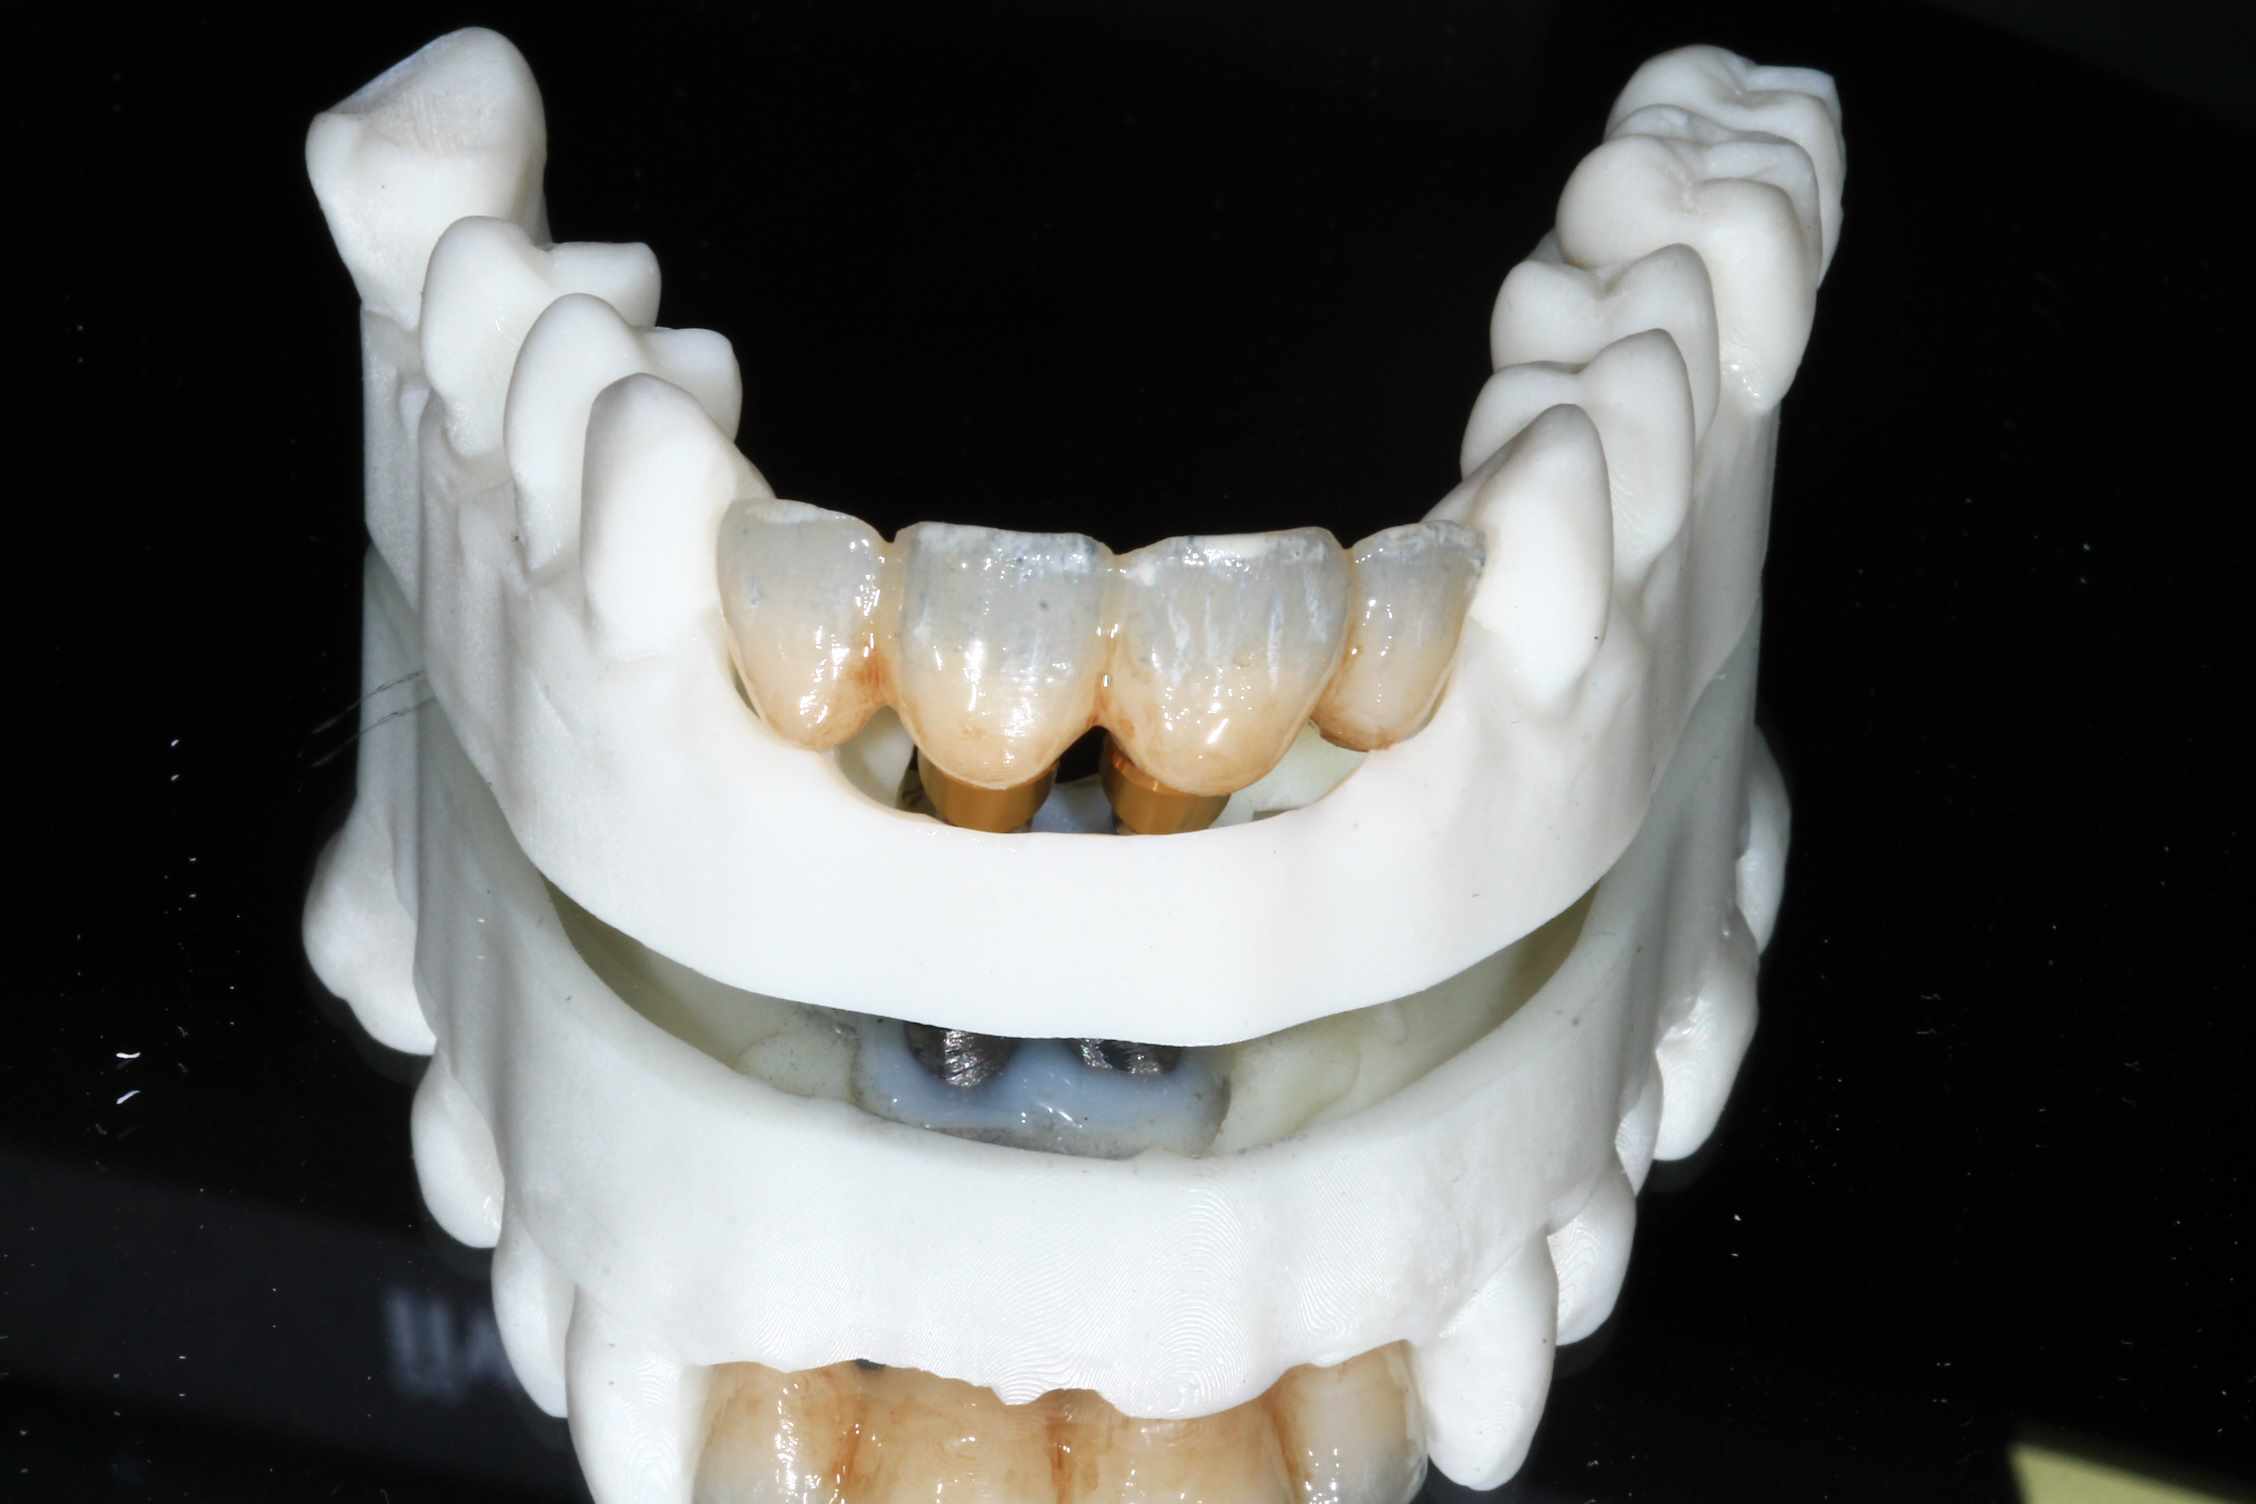

les 4 incisives sup sont à bout de souffle . Planification et export du guide résine avec blueskyplan. Export du modèle osseux et simulation de la chirurgie, comme d'hab selon mon protocole.

Quand les implants sont peu nombreux et proches, un guide résine est suffisant. C'est alors beaucoup plus rapide.

Pré-op :

simulation de la chir. scan, matching des elements avec medit design, finition du bridge dana meshmixer.

Chir : extraction, implant flapless et pose du bridge imprimé Flexera rosenscrew.

Resultat a une semaine, 3 mois et bridge Full zircone katana maquillé MyIO rosensrew.